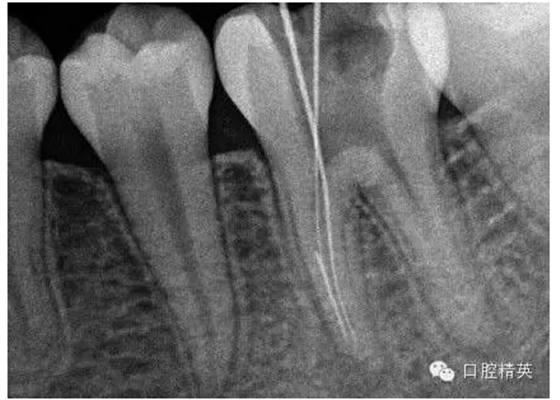

5, 插針確定斷針根管,為近舌根管,插針有阻力,EDTA封存一周復(fù)診。。。